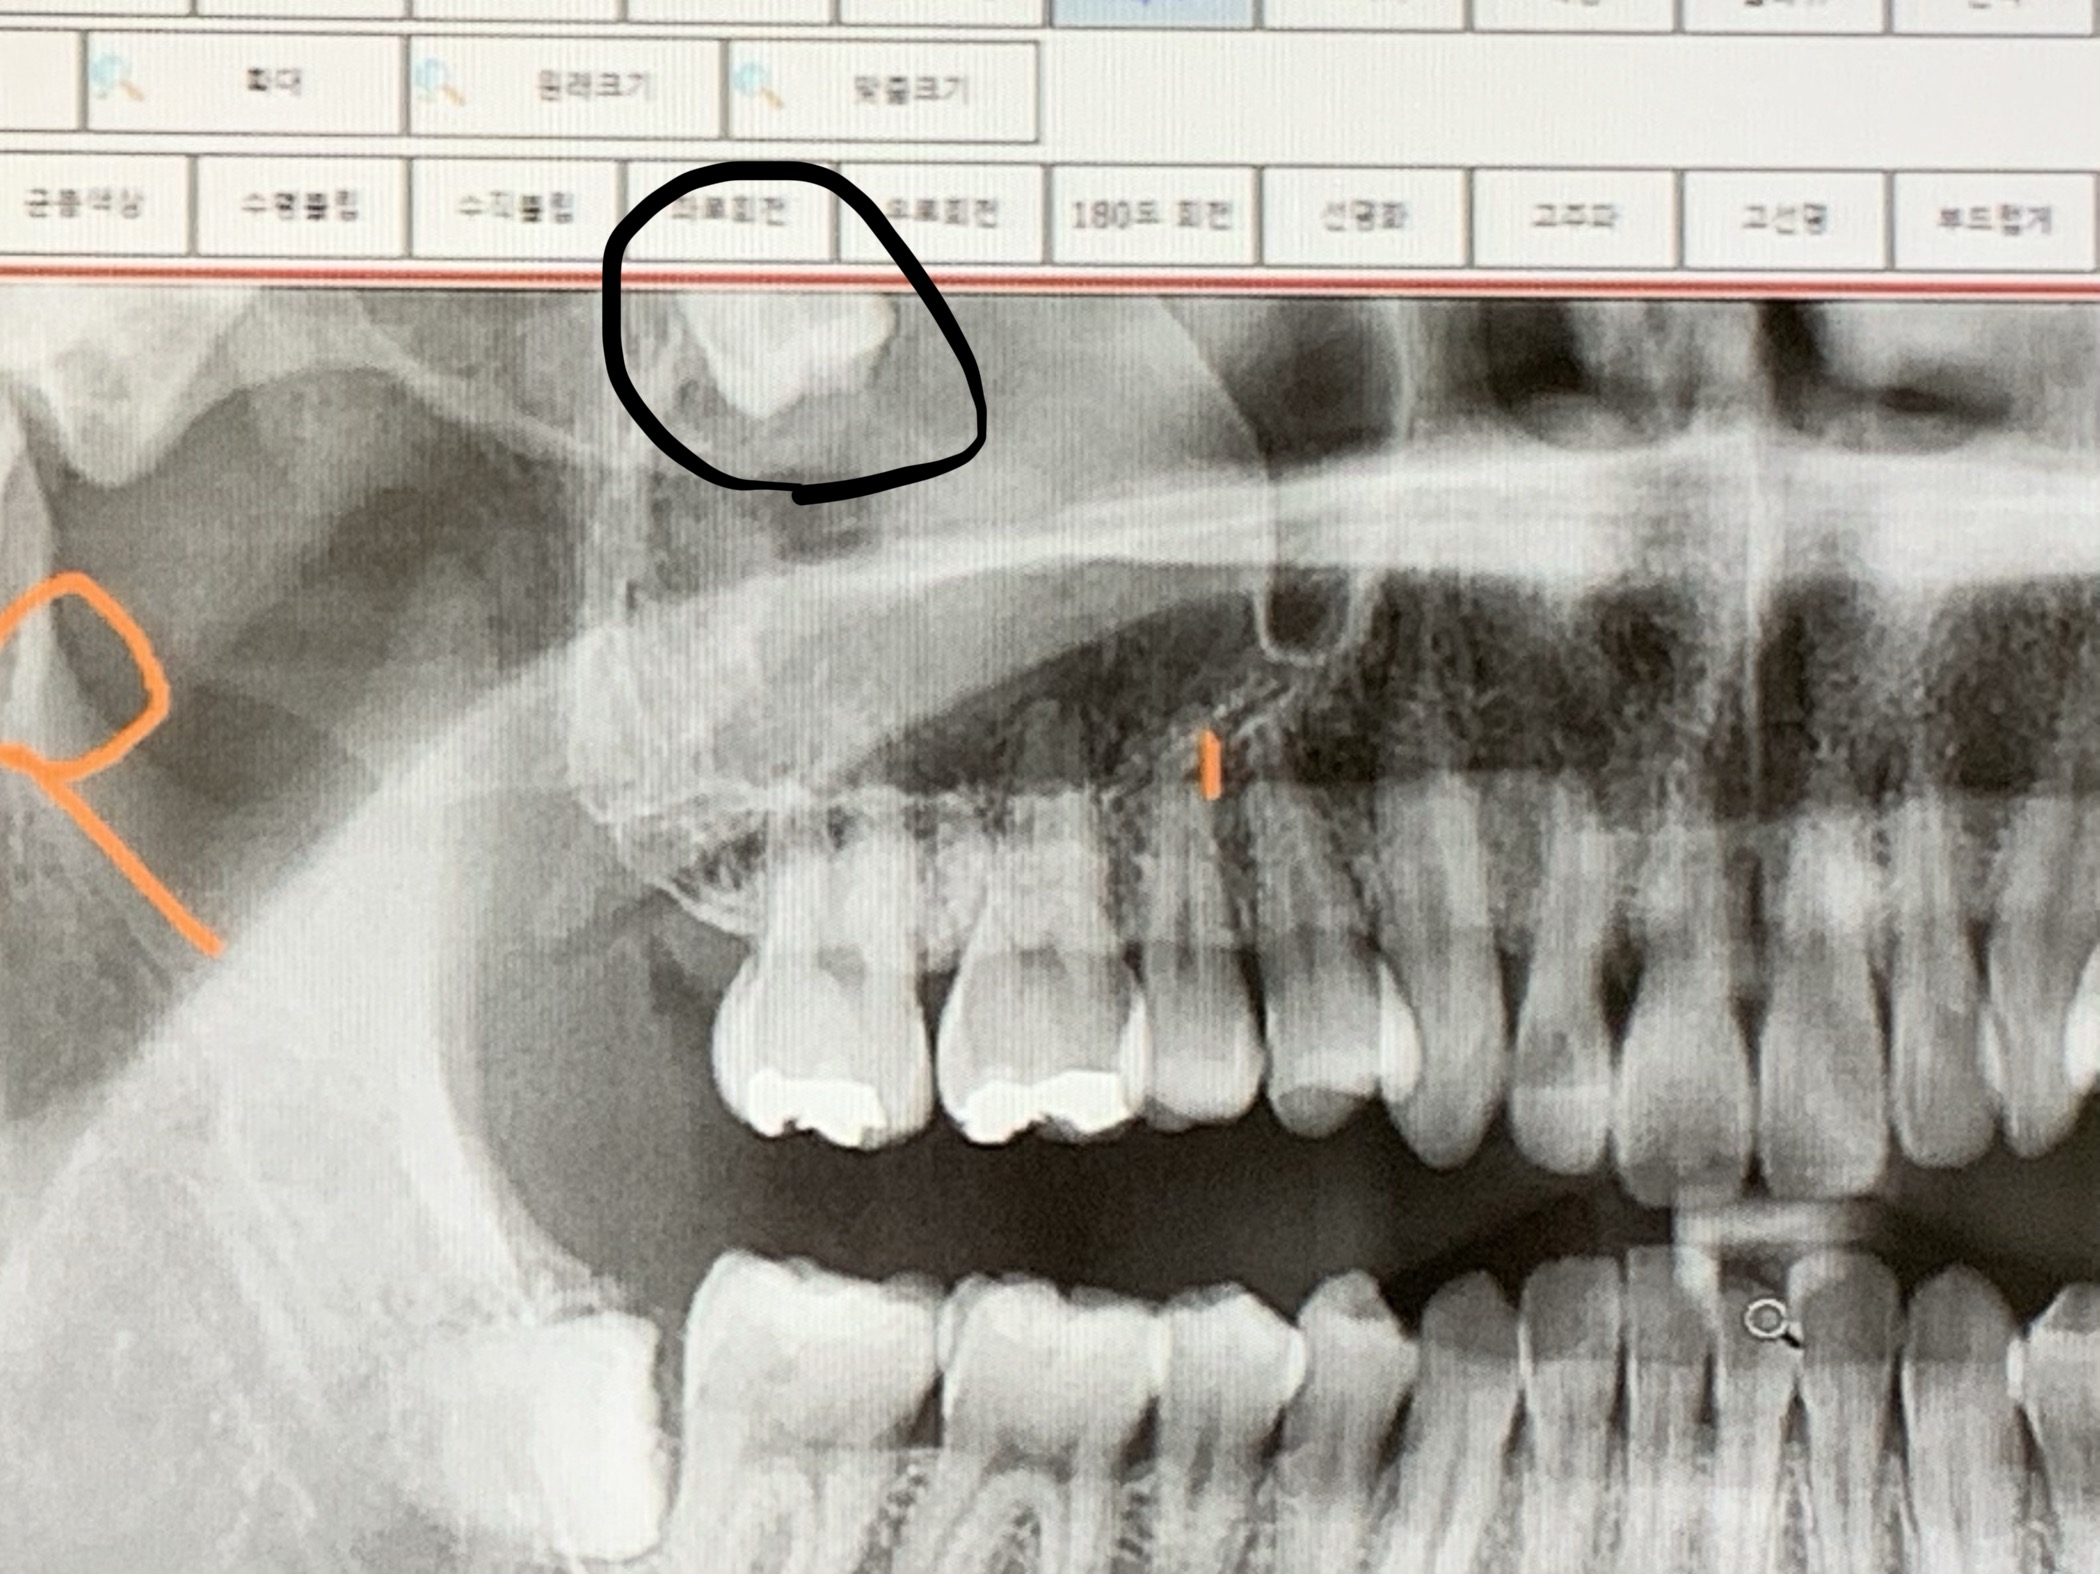

[유머] 흔치 않은 매복니를 가진 사람 [20]

설마 오른쪽 눈 저거 이빨이야?

"제발...일상생활에 지장이 가지 않는거라면 수술하지 말아주세요...!" 대학병원에서는 가급적이면 환자에게 수술받지 말라는 썰을 들은 것 같은데. 일단 저기에 난 이빨 뽑으려면 안면 부근의 뼈는 물론이고 신경까지 까야하는 난이도 헬 수술이 될거라서...

안구 찌르면 저건 어떻게 빼야 됨...?

입 천장 통해서 눈 아래로 하는 식으로 하지 않을까? | 26.03.18 06:21 | | |

저건 어찌빼냐?;; 눈아래있는데 ㄷㄷ

저거 뽑을라면 얼굴을 갈라야하는거야...?

저정도면 대학병원 가야겠는데 ㅋㅋㅋㅋ 안그래도 신경 많이 몰려있는부위인데 ㅋㅋㅋㅋ

내 동생은 코로 갔음

나도 눈 근처에 있는데 반가워 동지 ㅋㅋ